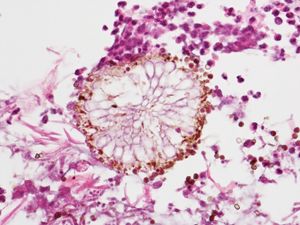

현미경 검사에서 ''아스페르길루스'' 종은 Gridley 염색 또는 고모리 메테나민-은과 같은 은 염색으로 확실하게 입증된다.[27] 이것들은 곰팡이 벽을 회색-검정색으로 만든다. ''아스페르길루스'' 종의 균사는 직경이 2.5um ~ 4.5um이다. 그들은 격막 균사를 가지고 있지만,[28] 이것들은 항상 뚜렷하지 않으며, 이러한 경우 접합균류로 오인될 수 있다.[27] ''아스페르길루스'' 균사는 약 45°의 예각에서 진행적이고 주로 이분법적 분지를 갖는 경향이 있다.[27]